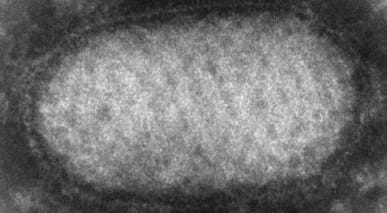

Вирус Эбола

Самые опасные инфекционные заболевания человека и их влияние на жизнь людей.